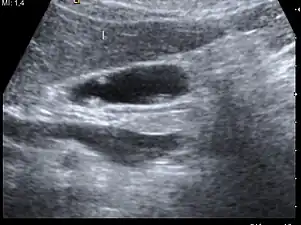

| A polyp in the gall bladder as seen on ultrasound |

Diagnosis is typically by ultrasound or CT imaging.